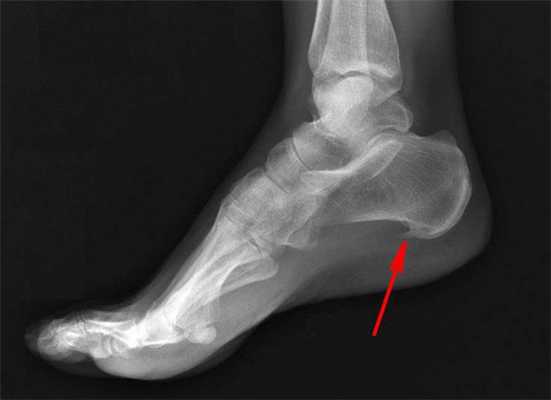

Поскольку продольное плоскостопие часто осложняется образованием пяточной шпоры, т. е. формированием на подошвенной части стопы или у ахиллова сухожилия костного выступа, при выполнении оперативного лечения, как правило, удаляют и его.

Каждая операция отличается не только своими особенностями проведения, но и показаниями. Поэтому выбор конкретной методики решения проблемы плоскостопия осуществляется строго индивидуально.